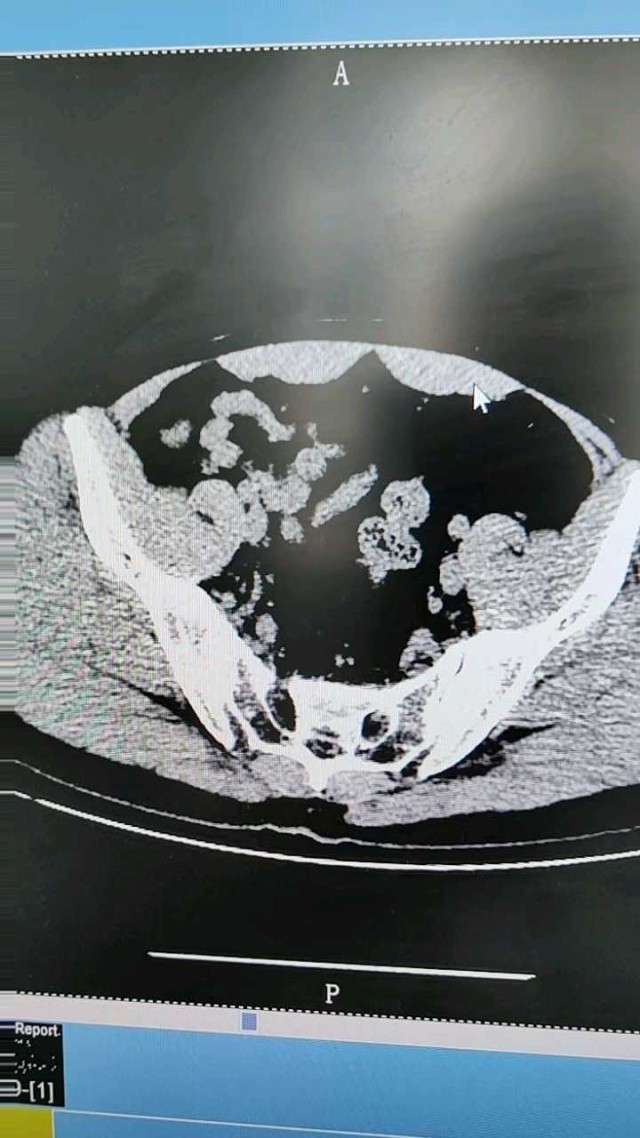

一例骨盆严重碾压伤,膀胱破裂,尿道断裂,腹股沟阴囊撕裂,睾丸脱出

病例信息男性,40岁,车祸致骨盆碾压,右侧腹股沟阴囊会阴撕裂,双侧睾丸脱出,试插导尿管,注生理盐水200mL抽出40mL鲜红血性液体,左髋关节畸形,左大腿广泛挤压,血压60/40mmHgCT扫描显示骨盆骨折,骶骨粉碎性骨折,耻骨联合分离,左髋关节脱位,腹腔积液诊断考虑:失血性休克,膀胱破裂,腹腔积液,腹股沟、阴囊、会阴撕裂伤,睾丸脱出输血输液升压维持生命体征,急诊开腹手术探查,术中发现回肠破裂,膀胱破裂,前列腺与膀胱颈部离断,盆底骶尾部巨大血肿。多学科联合手术。骨科:髋关节复位,骨盆骨折二期处理创伤外科:回肠部分切除,腹腔引流,盆底纱布填塞压迫止血介入科:双侧骼内动脉栓塞止血泌尿外科:腹股沟、